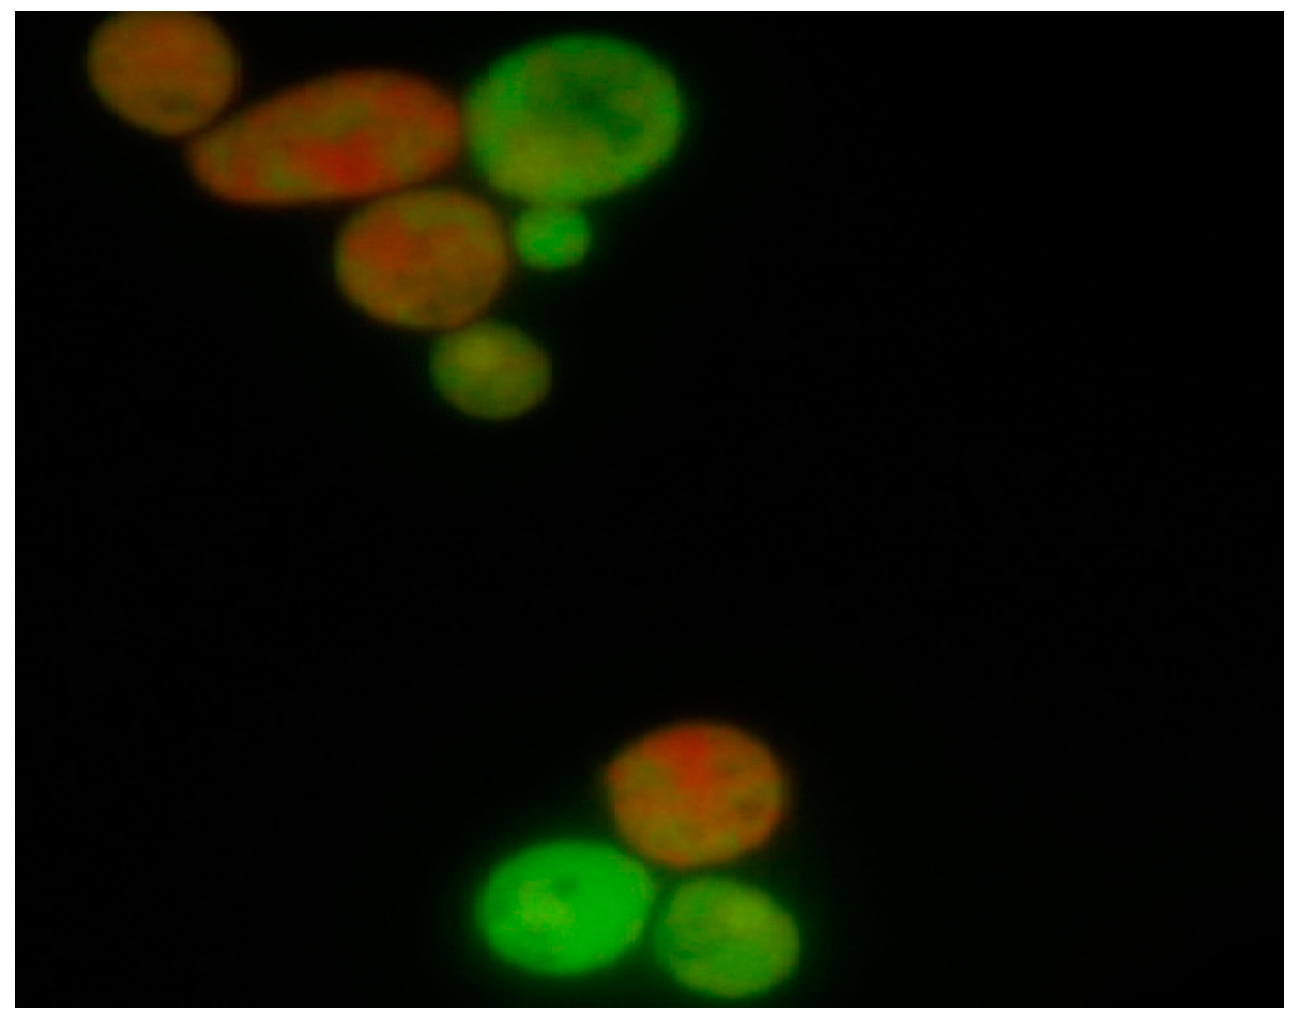

Analysis of C. albicans cells following 18 h in vitro exposure to oleuropein indicated a cytotoxic effect of oleuropein that was concentration-dependent. Further, intergroup comparison of viable vs. dead cells using the Pearson chi-square test revealed statistically significant differences (p < 0.05) between tested concentrations. In the samples treated with concentrations, 1.25 mg·mL−1 and 0.195 mg·mL−1 of oleuropein apoptosis was a predominant type of cell death. Differentiation between viable and dead cells after treatment with the test agent and the altered morphology of the nuclear chromatin visualized by fluorescence microscopy is shown in Figure 1.

Figure 1.

Appearance of C. albicans blastospores treated with oleuropein following staining with ethidium bromide and acridine orange according to the fluorescent-dye exclusion method: viable normal blastospores excluded ethidium bromide, and their nuclei were bright green with an intact structure. Non-viable cells had orange to red colored chromatin with organized structure. Apoptotic cells were bright green with highly condensed or fragmented nuclei.